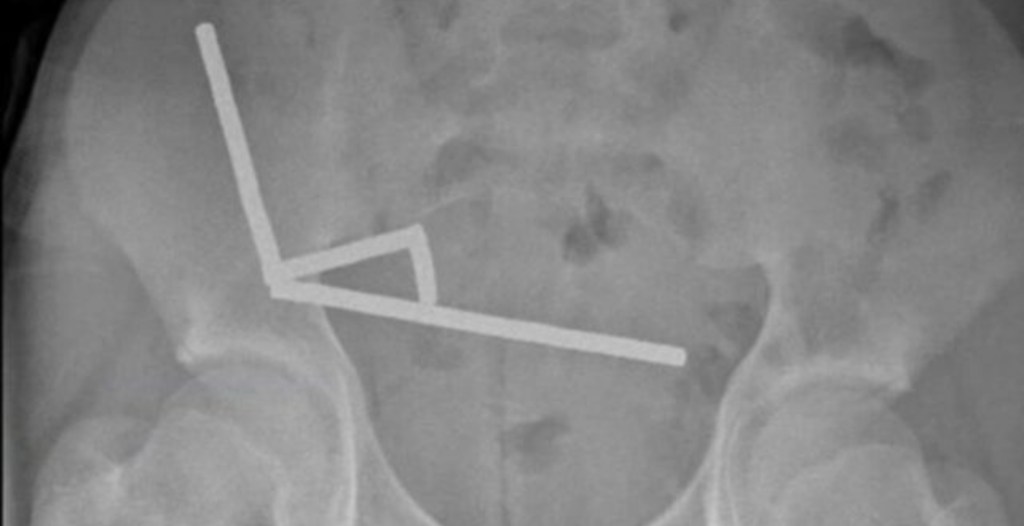

According to a recent case report published in The New Zealand Medical Journal, doctors at Tauranga Hospital had to go on a scavenger hunt in the kid’s abdomen, discovering four separate linear chains of metal objects.

Once inside, these tiny, brightly colored magnets, which are often marketed as harmless toys, did what magnets do. They are attracted to each other. Not only did they connect, they forcefully squeezed separated loops of the boy’s small bowel and caecum together.

This created patches of pressure necrosis, the medical term for tissue dying from a lack of blood flow. The surgical team had no choice but to remove part of his bowel. Thankfully, he recovered.